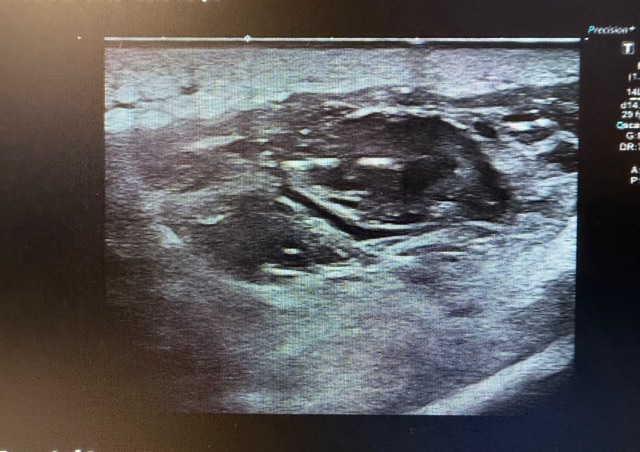

Hallazgos ecográficos

La ecografía muestra una lesión sólida hipoecoica, heterogénea y de contornos irregulares, situada entre la musculatura gemelar lateral y la musculatura peronea, con tamaño aproximado de 2,6–3,2 cm. Presenta áreas anecoicas compatibles con degeneración quística, pequeños focos hiperecogénicos sugestivos de calcificaciones y engrosamiento fascial con pérdida de la arquitectura normal. El estudio Doppler identifica vascularización interna arterial y venosa. Los hallazgos son compatibles con lesión mesenquimal profunda y potencialmente agresiva.